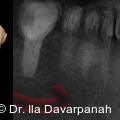

Die moderne Implantologie vereint heute funktionelle Stabilität mit höchsten ästhetischen Ansprüchen. Gerade im Frontzahnbereich hängt der Behandlungserfolg entscheidend von der präzisen Planung, der gewebeschonenden chirurgischen Umsetzung und einer frühzeitigen prothetischen Integration ab. Fotos: © Dr. Ila Davarpanah